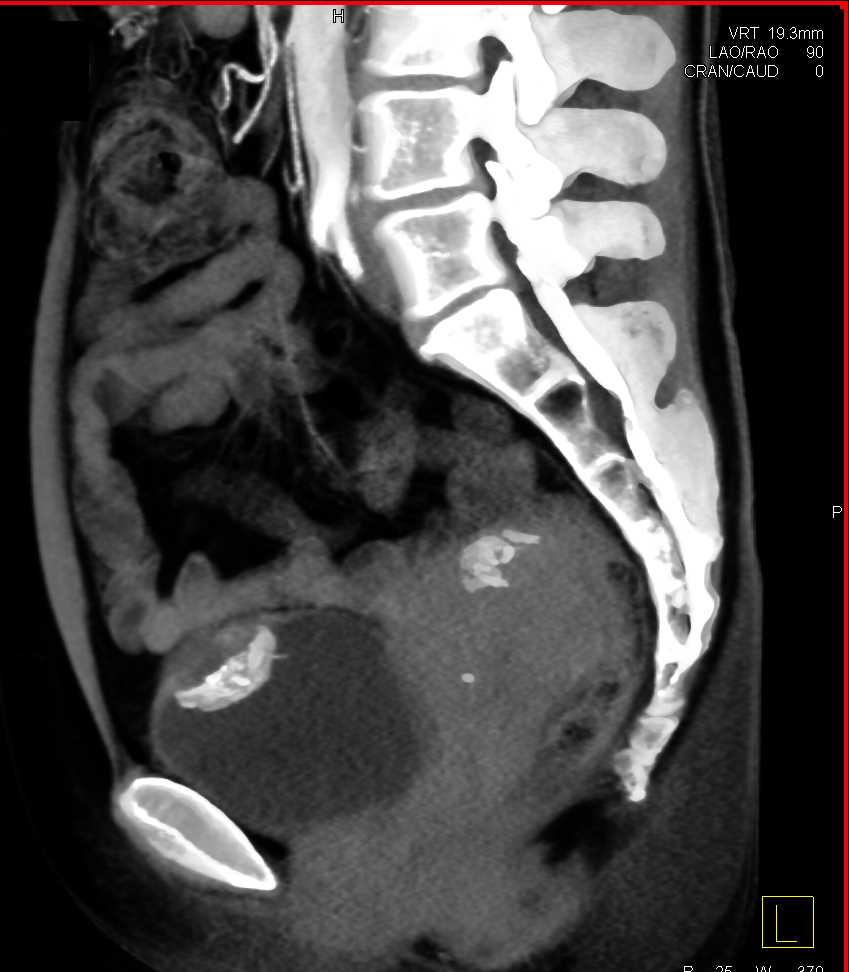

Urachal Carcinoma of the Bladder